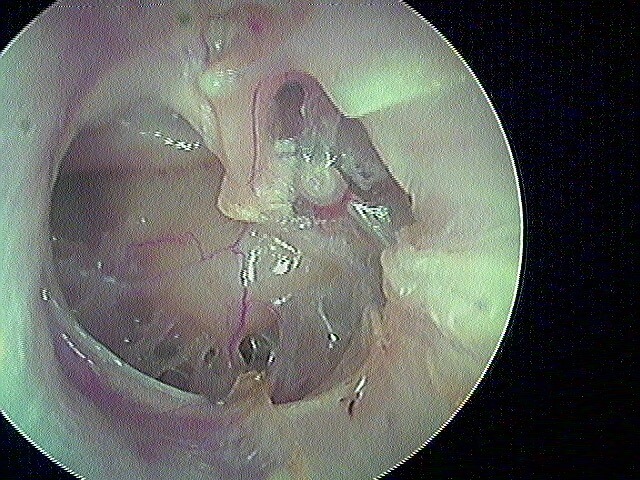

L' aspect post-opératoire de myringoplastie avec du fascia, 30 ans après:

L' aspect à long terme parfois post-aérateur avec séquelle fibro-adhésive

Mais aussi parfois de perforation séquellaire post-aérateur: